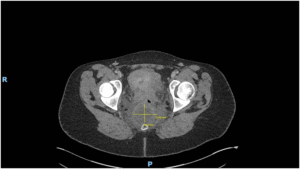

Imaging via MRI and CT demonstrated a complex, encapsulated lesion with peripheral enhancement and restricted diffusion. Multidisciplinary evaluation suggested a congenital epidermoid or duplication cyst. Given the absence of malignancy and surgical complexity, a conservative management strategy was adopted.

Figure 1: Figure 1 Duplication cyst 2025 MRI sagittal plane

Figure 2: Figure 2 Duplication cyst 2025 MRI sagittal plane

Figure 3: Figure 3 Duplication cyst 2020 Coronal plane

Figure 4: Figure 4 Duplication cyst 2020 sagittal plane

Figure 5: Figure 5 Duplication cyst axial 2020 plane post cystic aspiration

Figure 6: Figure 6 Duplication cyst 2025 sagittal plane

Figure 7: Figure 7 Duplication cyst 2025 MRI axial plane

Figure 8: Figure 8 Duplication cyst 2020 axial plane